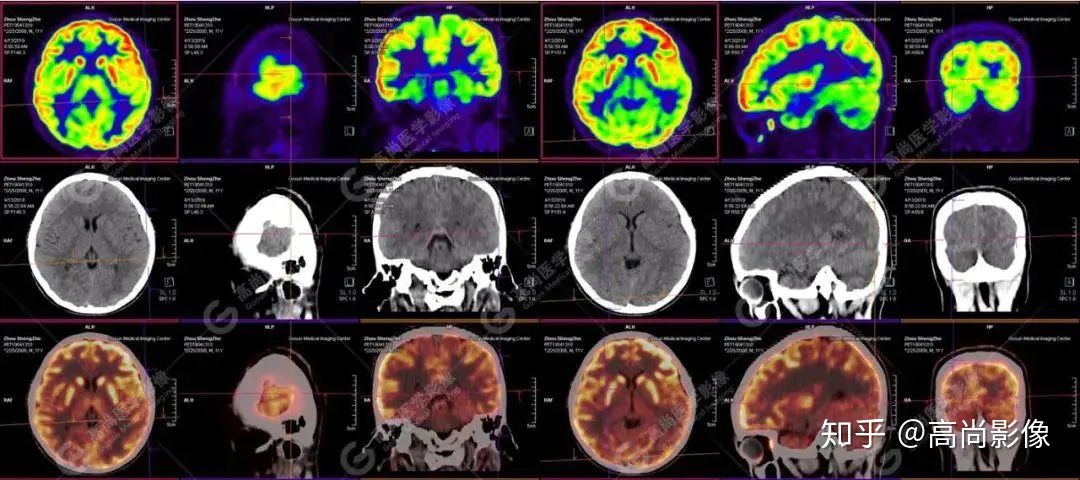

【病史摘要】男性,11歲;9歲時(shí)無(wú)明顯誘因癲癇發(fā)作,發(fā)作時(shí)雙眼上翻,意識(shí)不清,全身抽搐,每年發(fā)作4~5次,近期未行腦電圖及MRI檢查。

【PET/CT 】

提示: 大腦左側(cè)頂葉、顳葉(上部)及右側(cè)額葉、枕葉、顳葉(下部)腦皮質(zhì)代謝廣泛減低,尤以右枕葉為著,多考慮與癲癇發(fā)作相關(guān)。